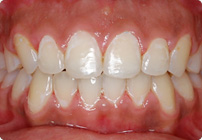

Masculino

Antes

Despues

Caso: 11 años

Adolescente: Clase II

Mordida Cruzada Posterior

Sin extracción

Sin uso de expansores

6 alambres superiores

5 alambres inferiores

Sin uso de elásticos

Retenedores: Interior Fijo de TMA y Hawley en superior

Tiempo de tratamiento: 14 Visitas